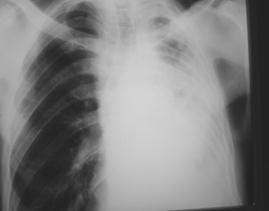

Рис. 7. Обширное затемнение (

экссудативный плеврит

): смещение органов средостения в противоположную сторону